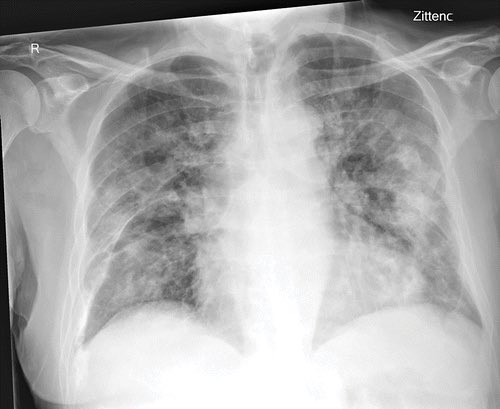

5/ As anyone who’s actually looked after severe COVID will tell you, this isn’t flu. And COVID itself is quite easy to spot on blood tests:

X-rays show severe changes in lungs:

- high CRP

- a specifically low white cell count (lymphocytes)

- low platelets

- very high d-dimer

X-rays show severe changes in lungs: